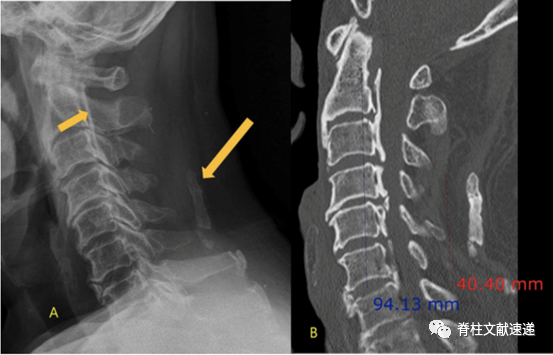

2.将项韧带骨化分成5型,如下图所示,分别为局灶型(A)、连续型(B)、间断型(C)、混合型(D)、其他型(E);

3.局灶型和连续型提示颈椎不稳,间断型、混合型和其他型提示OPLL的可能;

4.局灶型是最常见的项韧带骨化类型;

5.C4/5和C5/6是最常发生的节段。